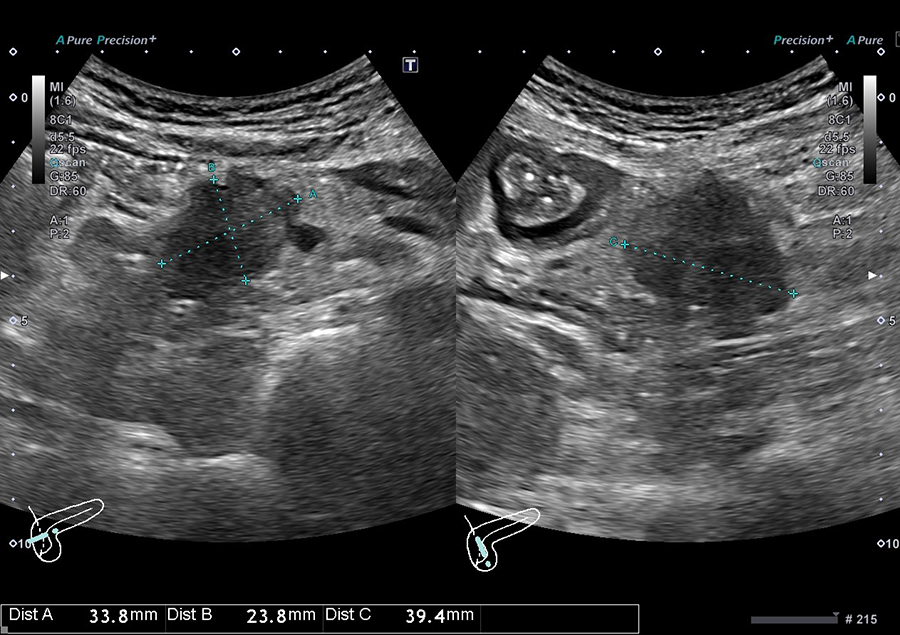

02.最新の超音波診断装置を導入

当院では、キヤノンメディカルシステムズ株式会社の超音波診断装置「Aplio a Verifia」を導入しています。

- ノイズを低減し、クリアな画質で病変を検出

- 従来の腹部エコーに比べ、広範囲を一度に撮影可能で、病変の位置がより分かりやすく確認できます

- 送信・受信技術(Advanced Sync Pulser と Advanced Beam Receiver とMulti-Harmonic Compounding)により、高精細な画像を提供

- 低流速血流の観察に適したSMI で、病変を詳細に観察

高精細な画像と優れた解析技術により、正確に観察することが可能です。

信頼性の高い検査結果を患者さまにお届けします。